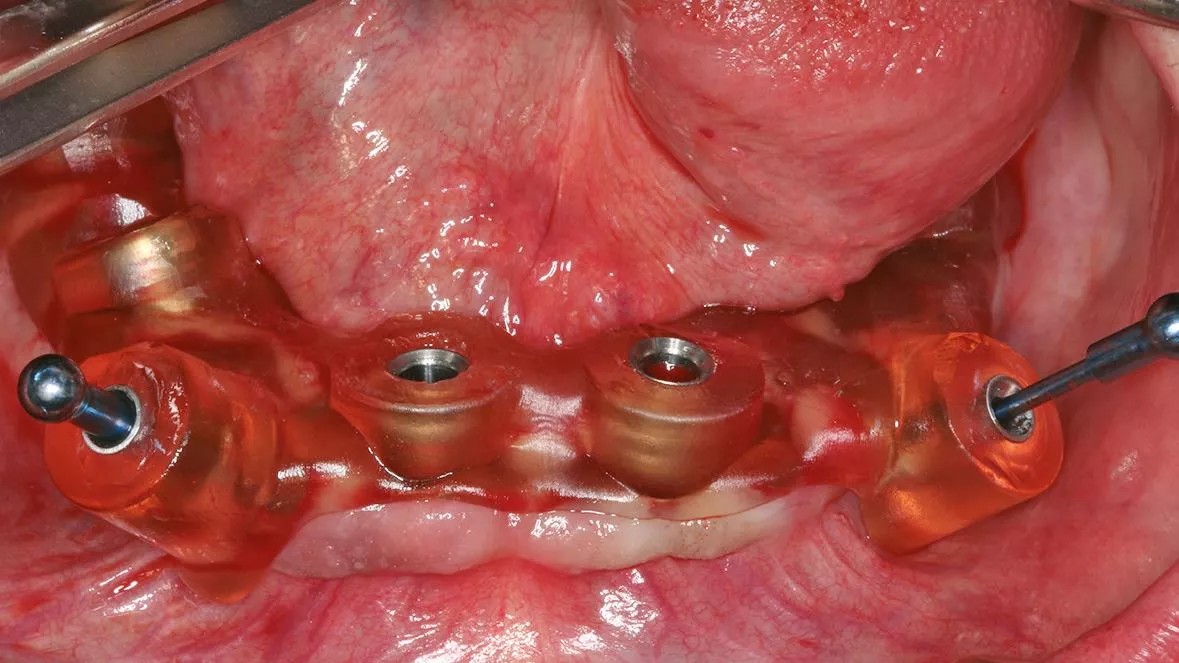

Dies erfordert aber gerade beim digitalen Scan eine vollständige Darstellung des Gaumendachs bis zur A-Linie. Im zahnlosen Unterkiefer ist eine Abstützung über den retromolaren Bereich möglich, dieser lässt sich aber je nach Intraoralscanner oftmals nicht vollständig abbilden. Bei einer Sofortimplantation können die Zähne, die nicht durch ein Implantat ersetzt werden zunächst für die Abstützung der Schablone belassen werden. Alternativ hat sich auch die Verwendung von Fixationspins etabliert, mit denen die Schablone auf der Schleimhaut abgestützt werden kann [13] (Abb. 9-10).

Dieses Vorgehen wird vor allem bei der sogenannten Flapless-Surgery verwendet, wo auf eine Mobilisation des Mukoperiostlappens verzichtet wird [10]. Bei der Auswahl des Aufbereitungsinstrumentariums kann für eine Navigationsschablone lediglich mit einer Pilotbohrung gearbeitet werden und es folgt die weitere Aufbereitung mit dem standardmäßigen Instrumentarium. Alternativ wird ein schaftgeführtes Instrumentarium über eine Masterhülse verwendet [2]. Die Vorteile der voll geführten Aufbereitung zeigen sich in einem geringeren Risiko von Verkippungen oder einer zu tiefen Aufbereitung der Kavitäten. Beim Einsetzen der Bohrschablone mit Fixationspins können diese

im Oberkiefer bei dünner Kortikalis oftmals durch ein festeres Einpressen positioniert werden. Im Unterkiefer wird über die Hülse für den Fixationspin in der Regel eine Vorbohrung notwendig. Nach der genauen Lagesicherung der Navigationsschablone kann dann die komplette Bohrerabfolge geführt bis zur Implantatinsertion angewendet werden. Im Anschluss werden die bei der Planung definierten geraden und angulierten Abutments eingesetzt und die Titanzylinder für das Einkleben des Provisoriums fixiert [1]. Nach dem Einkleben der Zylinder in das Provisorium muss diese nochmals ausgearbeitet werden und die Sofortversorgung ist abgeschlossen (Abb. 11-12).